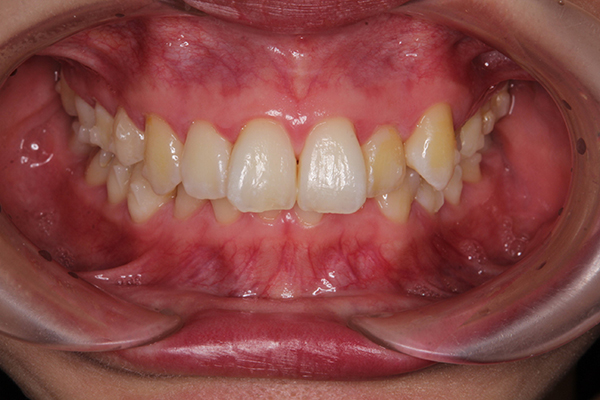

アタッチメントがついた写真が、こちら。

ぽつぽつと小さなものが並んでついていて

ちょっとかわいいです。笑